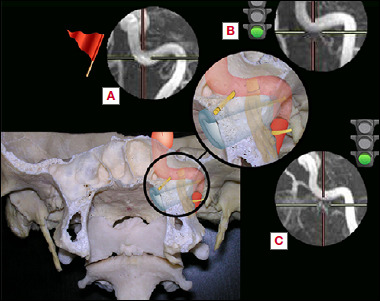

Objective: Skull base anatomy around the internal carotid artery (ICA) is extremely complex. Among anatomical landmarks studied, the vidian canal has been thoroughly evaluated, unlike the vidian nerve (VN). Our aim is to evaluate the VN-ICA relationships, and understand their role in terms of surgical planning.

Methods: Fifty MRI examinations of 100 healthy petro-spheno-clival regions were reviewed in order to evaluate the relationship between the vidian nerve axis (VNA) and the petrous ICA. Twenty-seven cases of expanded endonasal approaches to petrous apex region were evaluated to check the VN-ICA relationship intraoperatively.

Results: MRI evaluations showed that, in 23% of cases, the VNA was below the edge of the ICA, in 45% it was at the edge of the ICA and in 32% it ended up above the edge of the ICA. Surgically speaking, in 9 of 28 petrous apex approaches, the VN ended above the inferior edge of the petrous carotid.

Conclusions: MRI evaluation adds useful information in planning the surgical approach to petro-spheno-clival regions, even if the identification of VNA, in these cases, may not be radiologically possible. Surgical experience confirms the importance of VN identification in guiding the surgeon in complex cases, and also outline the possible risks of relying only on this landmark.